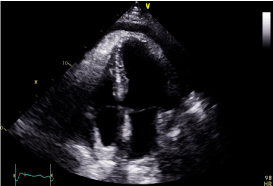

Cardiac MRI showed mildly increased left ventricular (LV) volume indices (End Diastolic Volume - 148mls, End Diastolic Volume Indexed - 71mls, and End Systolic Volume - 75mls, End Systolic Volume Indexed - 31mls) and mildly impaired LV systolic function with LV ejection fraction 48%, normal right ventricular systolic function, and a well circumscribed lesion in the basal lateral wall (Figures 3 and 4). The lesion was hypointense in TruFISP, hyperintense in T1 and T2 weighted images which suggested the lesion did not contain water or fat.  The lesion showed strong homogenous high intake enhancement with gadolinium contrast both in the early and late phase suggesting it was highly vascular. The perfusion study demonstrated a fixed perfusion defect around the lesion. In the gadolinium study, there was no evidence of LV or RV thrombus in the early phase while in the late phase, there was a patch of full thickness late gadolinium enhancement (LGE) around the lesion (Figure 5).

Figure 3. Well circumscribed hypointense lesion in basal lateral wall of left ventricle seen in short axis SSFP cine (Blue arrow).